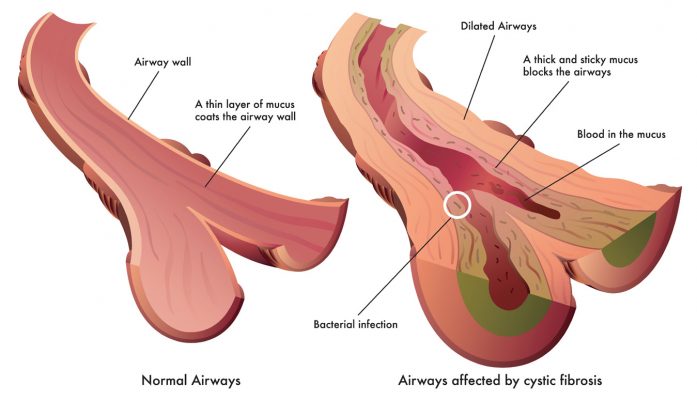

Η συσσώρευση κολλώδους βλέννας στους πνεύμονες μπορεί να προκαλέσει αναπνευστικά προβλήματα και αυξάνει τον κίνδυνο λοιμώξεων των πνευμόνων. Με την πάροδο του χρόνου, οι πνεύμονες μπορεί να σταματήσουν να λειτουργούν σωστά. Η βλέννα φράζει επίσης το πάγκρεας (το όργανο που βοηθά στην πέψη), το οποίο εμποδίζει τα ένζυμα να φτάνουν στα τρόφιμα στο έντερο και να βοηθούν στην πέψη. Αυτό σημαίνει ότι τα περισσότερα άτομα με κυστική ίνωση δεν απορροφούν σωστά τα θρεπτικά συστατικά από τα τρόφιμα και πρέπει να καταναλώνουν περισσότερες θερμίδες για να αποφύγουν τον υποσιτισμό.

- συριγμός, βήχας, δύσπνοια και βλάβη στους αεραγωγούς (βρογχεκτασίες)